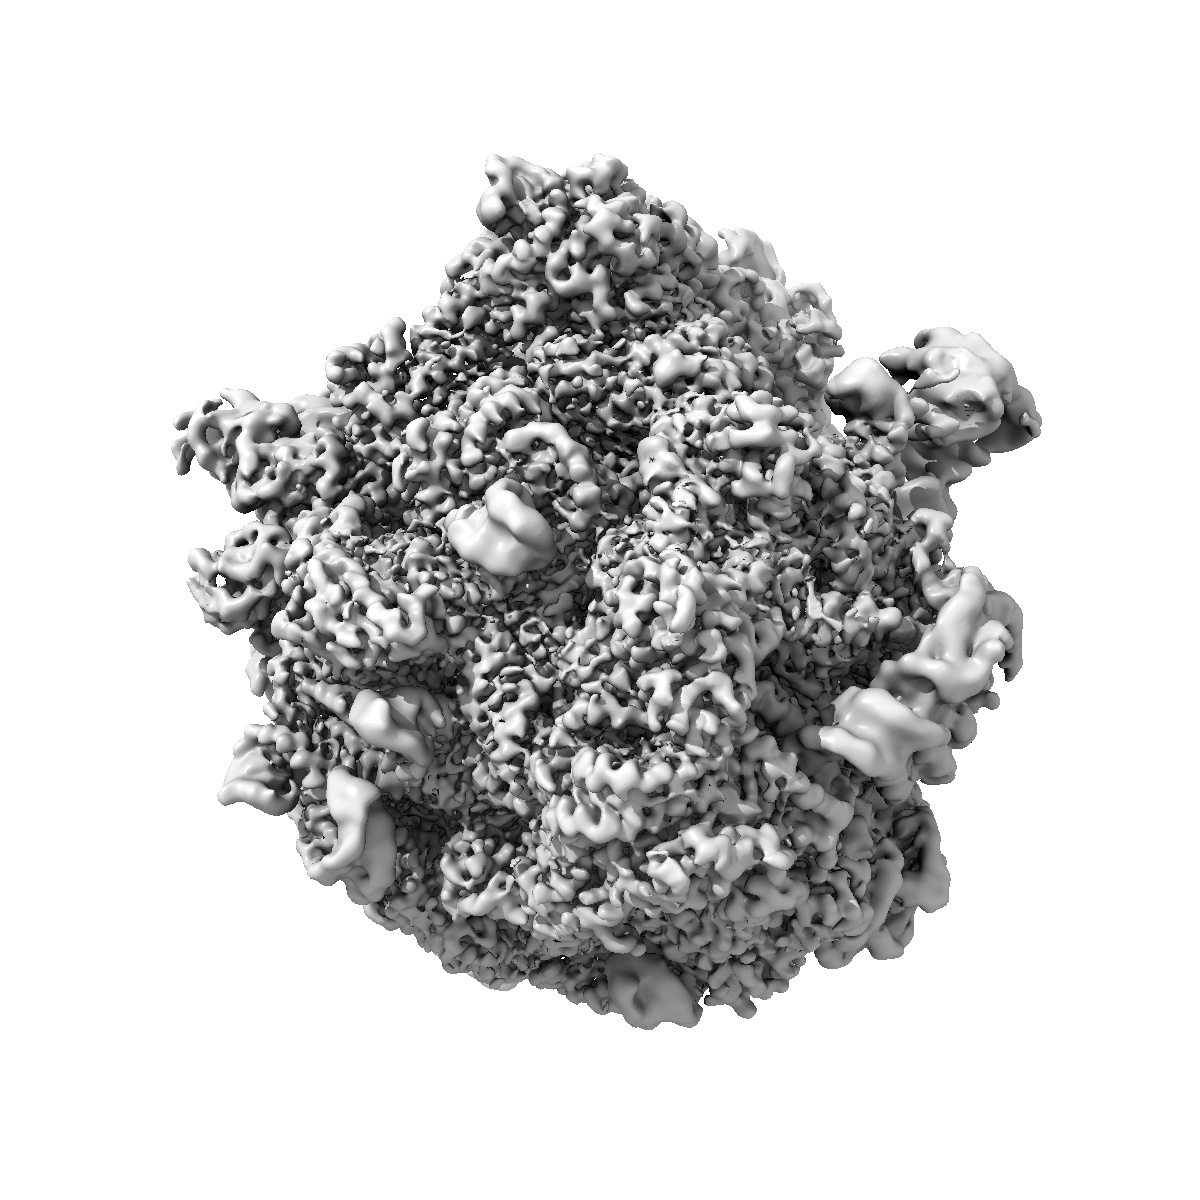

Pre-release fusidic acid-locked Escherichia coli 70S ribosome with Staphylococus aureus EF-G and FusB (FusB-EF-G-70S)

Single-particle

2.79 Å

Structural mechanism of FusB-mediated rescue from fusidic acid inhibition of protein synthesis.

Gonzalez-Lopez A , Ge X , Larsson DSD , Sihlbom Wallem C, Sanyal S , Selmer M

(2025) Nat Commun , 16 , 3693 - 3693